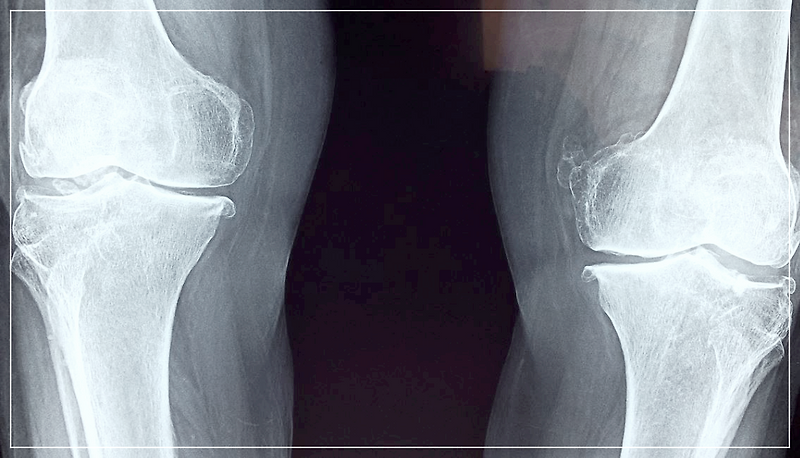

골다공증이란 대한민국 골다공증 환자수는 5년 사이에 30% 이상 급증했다. 골다공증은 노화로 인한 뼈의 밀...